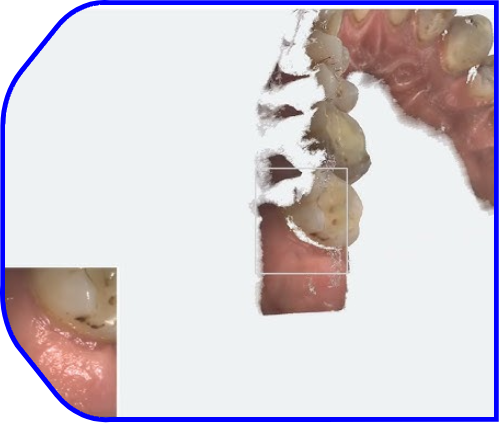

3DISC Heron™ IOS: Dijital Diş Hekimliği İçin Ağız İçi Tarayıcı

Hafif, ergonomik tasarımı ve sezgisel yazılımıyla dijital diş hekimliğine geçiş yapın

Dijital Diş Hekimliği İçin İleri Seviye İntraoral Tarayıcı